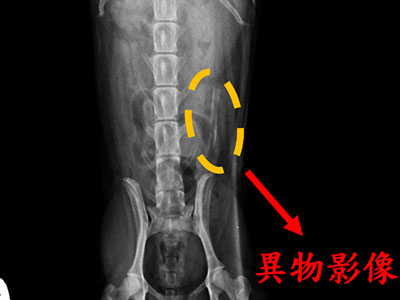

X光及腹腔超音波檢查在小腸段發現了一條高阻塞度的異物影像,疑似為骨頭且尖端銳利。